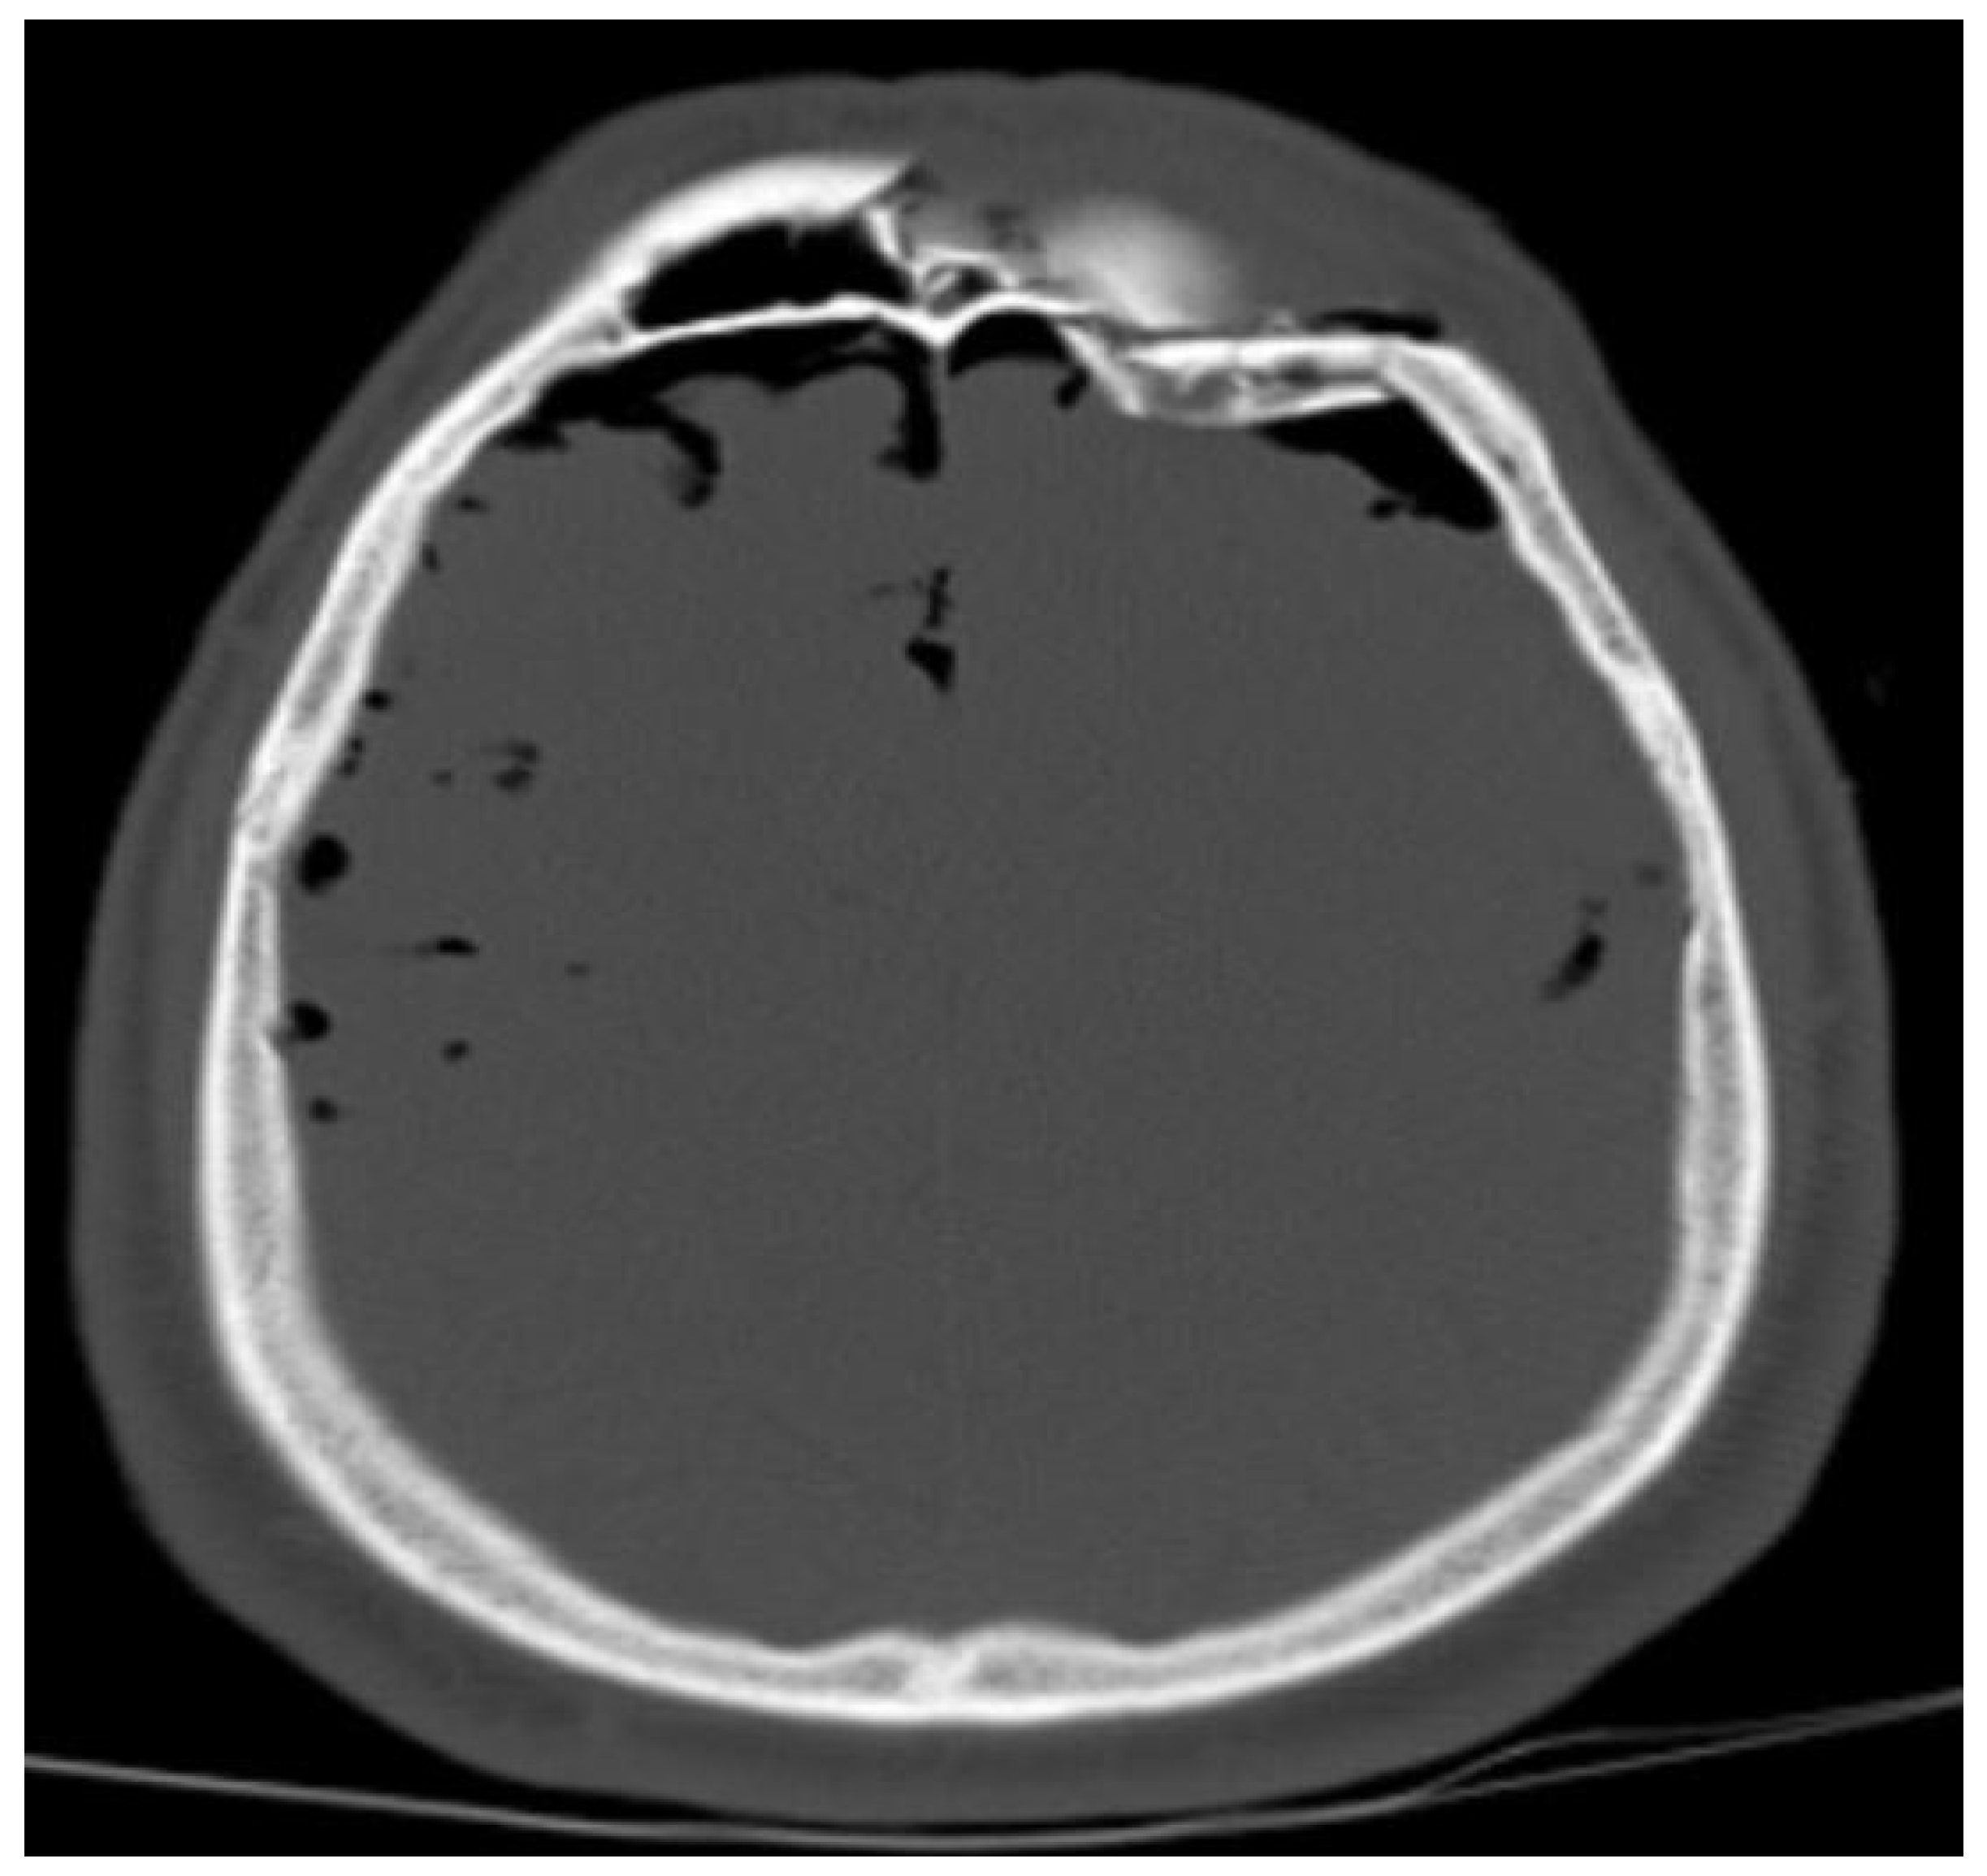

| Head | 5 (26.3) | 14 (73.7) | 13 (9.2) | 128 (90.8) | 18 (11.3) | 142 (88.7) | 0.027 |